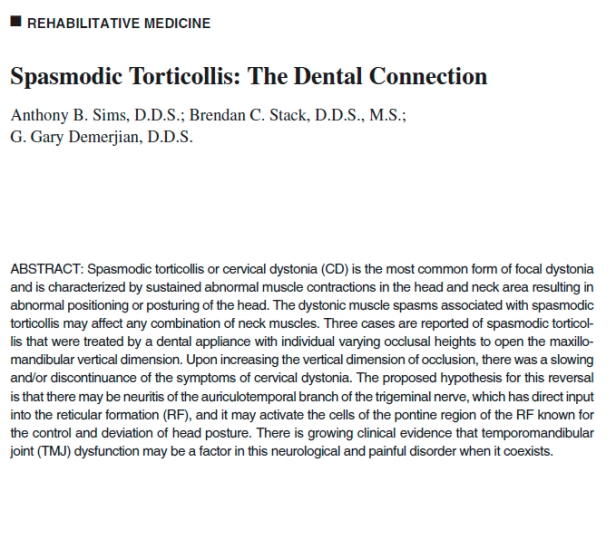

Comecei me aprofundar sobre trabalhos publicados nesta área. Um dos artigos que influenciaram a aceitar o paciente foi : Spasmodic Torticollis: The Dental Connection . Anthony b. Sims, D.D.S.; Brendan C> Stack, D>D>S> ;MS.;Gary Demererjian, D.D.S.

Spasmodic Torticollis: The Dental Connection . Anthony b. Sims, D.D.S.; Brendan C> Stack, D>D>S> ;MS.;Gary Demererjian, D.D.S.

Cara Maria Helena, lamentavelmente estes tratamentos são ainda efetuados por uma minoria de profissionais no mundo, tem colegas americanos que a tempo melhoram as distonias cervicais, melhorando a posição mandibular. No caso clinico que publiquei tem o link do artigo publicado em estados unidos,Spasmodic Torticollis: The Dental Connection

Anthony B. Sims, D.D.S.; Brendan C. Stack, D.D.S., M.S.;

G. Gary Demerjian, D.D.S.tenta mostrar esse link para os médicos que te tratam, se não consegues abaixar o artigo me fala que eu te envio por emai.